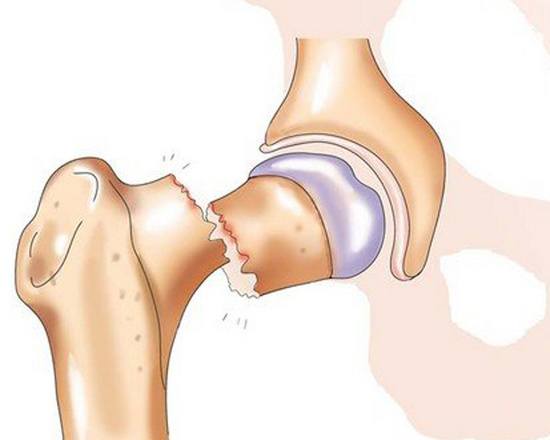

Перелом шейки бедра на рентгенограмме

Тазобедренный сустав – один из самых крупных суставов. Он выполняет опорную функцию и несет значительную нагрузку при беге и ходьбе. Сустав состоит из шаровидной головки бедра и глубокой округлой вертлужной впадины, окруженных капсулой и мощными связками. Еще одна крупная связка располагается прямо в центре сустава и соединяет дно вертлужной впадины с головкой бедра. В своей периферической части головка переходит в шейку, а шейка – в тело бедренной кости. Шейка расположена под углом к основной части кости, в области угла располагаются большой и малый вертелы.

Кровоснабжение головки осуществляется тремя путями. Первый – через сосуды, расположенные в капсуле сустава, второй – через артерии, проходящие внутри кости, и третий – через сосуд, расположенный внутри связки между головкой бедра и вертлужной впадиной. С возрастом кровоснабжение головки бедра ухудшается, сосуды сужаются, а артерия внутри связки полностью закрывается и перестает «работать». При переломах шейки проксимальный отломок лишается питания из внутрикостных сосудов. Артерий в капсуле оказывается недостаточно для адекватного снабжения кости кровью, поэтому проксимальный костный фрагмент не прирастает к дистальному, а в некоторых случаях и вовсе рассасывается. Такое состояние называется аваскулярным некрозом или остеонекрозом шейки и головки бедра.

Перелом шейки бедра на рентгенограмме

Тазобедренный сустав – один из самых крупных суставов. Он выполняет опорную функцию и несет значительную нагрузку при беге и ходьбе. Сустав состоит из шаровидной головки бедра и глубокой округлой вертлужной впадины, окруженных капсулой и мощными связками. Еще одна крупная связка располагается прямо в центре сустава и соединяет дно вертлужной впадины с головкой бедра. В своей периферической части головка переходит в шейку, а шейка – в тело бедренной кости. Шейка расположена под углом к основной части кости, в области угла располагаются большой и малый вертелы.

Кровоснабжение головки осуществляется тремя путями. Первый – через сосуды, расположенные в капсуле сустава, второй – через артерии, проходящие внутри кости, и третий – через сосуд, расположенный внутри связки между головкой бедра и вертлужной впадиной. С возрастом кровоснабжение головки бедра ухудшается, сосуды сужаются, а артерия внутри связки полностью закрывается и перестает «работать». При переломах шейки проксимальный отломок лишается питания из внутрикостных сосудов. Артерий в капсуле оказывается недостаточно для адекватного снабжения кости кровью, поэтому проксимальный костный фрагмент не прирастает к дистальному, а в некоторых случаях и вовсе рассасывается. Такое состояние называется аваскулярным некрозом или остеонекрозом шейки и головки бедра.